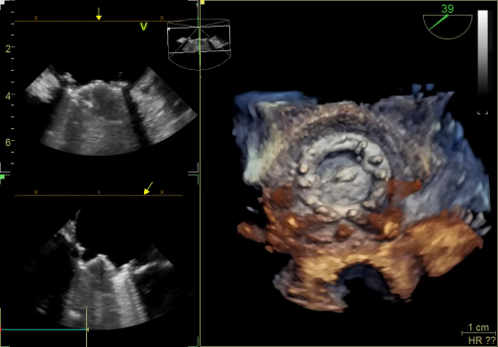

TEE, TEE and Floro showed both the leaflets to be stuck, almostno flow across the PV. The RV was higely dilated and there was severe RVdysfunction

Since TLT was not possible and surgeon refused for emergencyTranscatheter valve disruption was planned. The issues involve in the procedure were 1.Septal Puncture -due to pericardial patch in IAS, alteredanatomy due to Sx & ac dilatation of LA- Angle of puncture and Site ofpuncture. 2 Selection of wire3.Balloon- Size, make ( Compliant Vs NC), 4.Complication-like disc embolization, stuck disc leading to ac severe MA and strud fracture. The septa puncture was done as standard approach, a V18 wirewas parked in PV through a 7f Mullin sheath, Straight Turmo wire was was takenthrough a 6 JR to cross the valve and a 6 x 40 Armada balloon was dilatedacross the disc. Good acute result was obtained. The LA mean decreased from36-40 to 10-12mmHg. Post procedure the inotropic support, O2 demand decreasedover next 12 hr. However after 24 hr pt developed refractory RH failure and persistentanuria requiring SLED. And pt succumbed to the procedure 3 days after theprocedure.